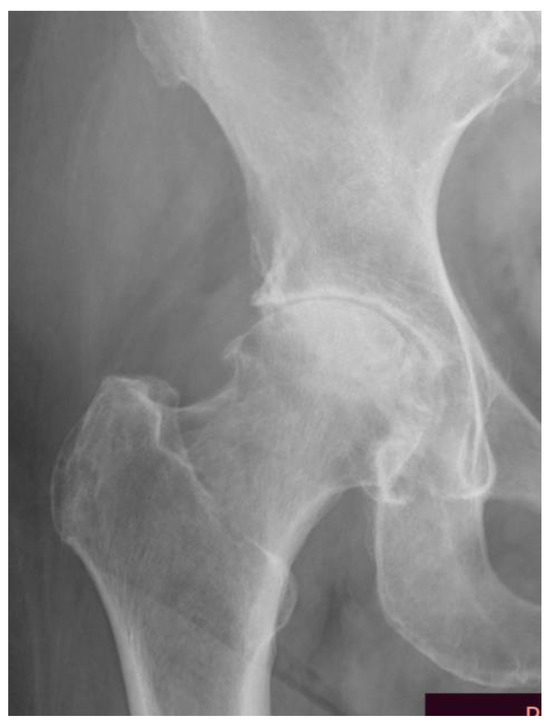

- Kellgren, J.H.; Lawrence, J.S. Radiological Assessment of Osteo-Arthrosis. Ann. Rheum. Dis. 1957, 16, 494–502. [Google Scholar] [CrossRef]

- Mark, D.; Kohn, B.A.; Adam, A.; Sassoon, M.D.; Navin, D. Classifications in Brief: Kellgren-Lawrence Classification of Osteoarthritis. Clin. Orthop. Relat. Res. 2016, 474, 1886–1893. [Google Scholar] [CrossRef]

| Grade | Radiological Findings |

|---|---|

| 0 | Normal |

| 1 | Doubtful narrowing of joint space and possible osteophytic lipping |

| 2 | Definite osteophytes, definite narrowing of joint space |

| 3 | Moderate multiple osteophytes, definite narrowing of joint space, some sclerosis, and possible deformity of the bone contour |

| 4 | Large osteophytes, marked narrowing of joint space, severe sclerosis, and a definite deformity of bone contour |